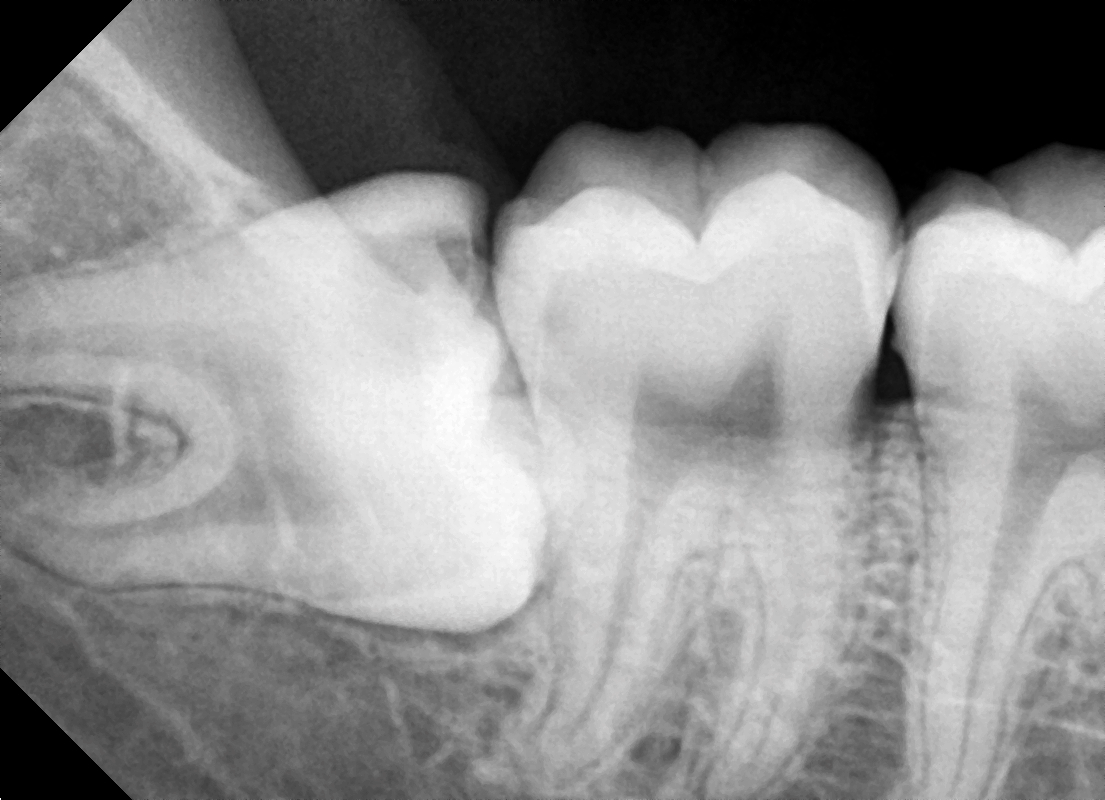

일단, 엑스레이를 보면

제가 빨간색으로 표기를 해 둔 ‘틈’ 이 있습니다.

근데, 이 틈이 거울이나

우리 눈으로 봤을 땐 틈이 없는 것 처럼 볼 수 있으나

실제로는 깊고 좁은 틈입니다.

즉, 여기서 음식 저류가 나타나게 될 텐데

양치질로 절대 닦아 낼 수 없는 곳입니다.

즉, 세균이 쉽게 번식이 되면서

광범위 충치들이 만들어질 수 밖에 없습니다.

딱, 발생 되기 좋은 환경이죠.

그래서, 이 곳을 기점으로 충치 및 염증이 발생될텐데

초기에는, 통증이나 불편함을 거의 못 느끼실 거예요.